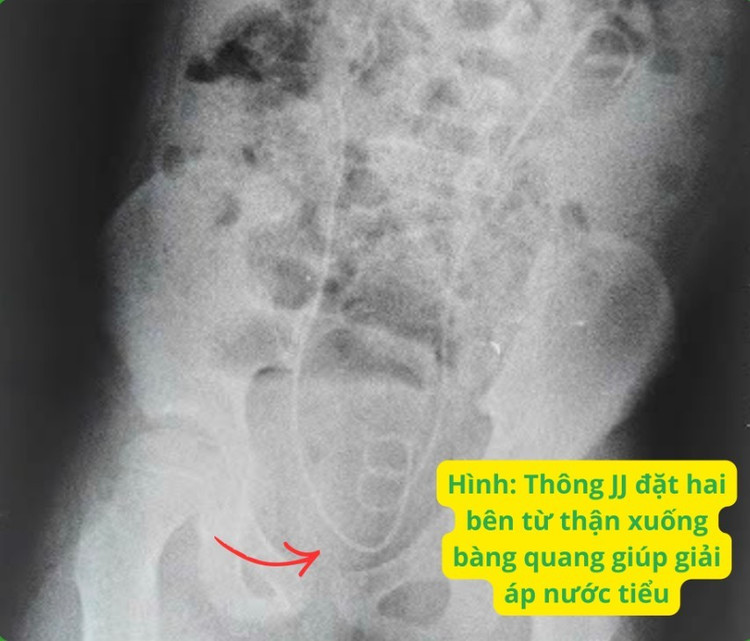

Bé ngay lập tức báo mổ cấp cứu và được ThS.BS Dương Hoàng Mai – khoa Thận niệu can thiệp soi bàng quang đặt JJ ngược dòng hai bên trong đêm.

Trong phẫu thuật ghi nhận sau khi đặt được thông JJ ngược dòng từ lỗ niệu quản 2 bên, rất nhiều nước tiểu đục thoát xuống kèm sỏi bùn từ lỗ niệu quản trái. Sau mổ 3 giờ, chức năng thận cải thiện rõ rệt và sau mổ 12 giờ thì trở về bình thường. Bệnh nhi đã hồi phục ngoạn mục nhờ sự kết hợp điều trị giữa hai chuyên khoa Thận niệu và Thận Nội tiết.

Soi bàng quang đặt JJ ngược dòng là một phương pháp can thiệp xâm lấn tối thiểu hiệu quả và phổ biến, được sử dụng để chuyển lưu nước tiểu, xử lý tắc nghẽn ở bệnh nhân bị sỏi niệu quản hoặc sỏi thận hai bên.